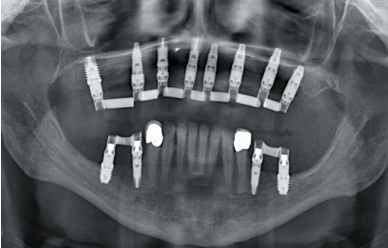

To start the diagnostic phase, a panoramic radiograph is performed that gives us an idea of the general condition of both jaws to start the treatment plan.

It shows that there is apparently some height in the maxillary ridge both anterior and posterior and a low dental nerve in the jaw that allows us to have a greater residual bone crest available for the insertion of the implants (Figure 3).

Subsequently, we proceed to perform a dental cone beam that offers a more accurate view of the type of implant rehabilitation that can be proposed. In the sections corresponding to the upper maxilla, there are areas where the direct insertion of the implants can be performed such as those corresponding to 16 and the central incisor zone of this quadrant (Figures 4-5) or in the second quadrant the area of the 27.

implant rehabilitation that can be proposed. In the sections corresponding to the upper maxilla, there are areas where the direct insertion of the implants can be performed such as those corresponding to 16 and the central incisor zone of this quadrant (Figures 4-5) or in the second quadrant the area of the 27. On the other hand, in the area corresponding to teeth 21 and 23 there is a significant horizontal atrophy, with a residual bone width of approximately 3.5 mm in the middle zone of the crest, with an enlargement in the most basal area of the same and conservation of both corticals. This leads to choose a split crest technique, in this case in two phases to achieve a greater final width and correct the inclination of the final implant as much as possible to achieve adequate aesthetics in the final prosthesis (Figure 6).

In the areas corresponding to teeth 11 and 13 the horizontal atrophy is even more marked. There is no trabecular bone separating the two corticals (vestibular and palatine) and the width is less than 2mm in some areas which is why block grafts are planned in this area. Short implants are planned in the mandible by direct insertion, and the area corresponding to the mandibular branch will be the donor area for the block grafts.